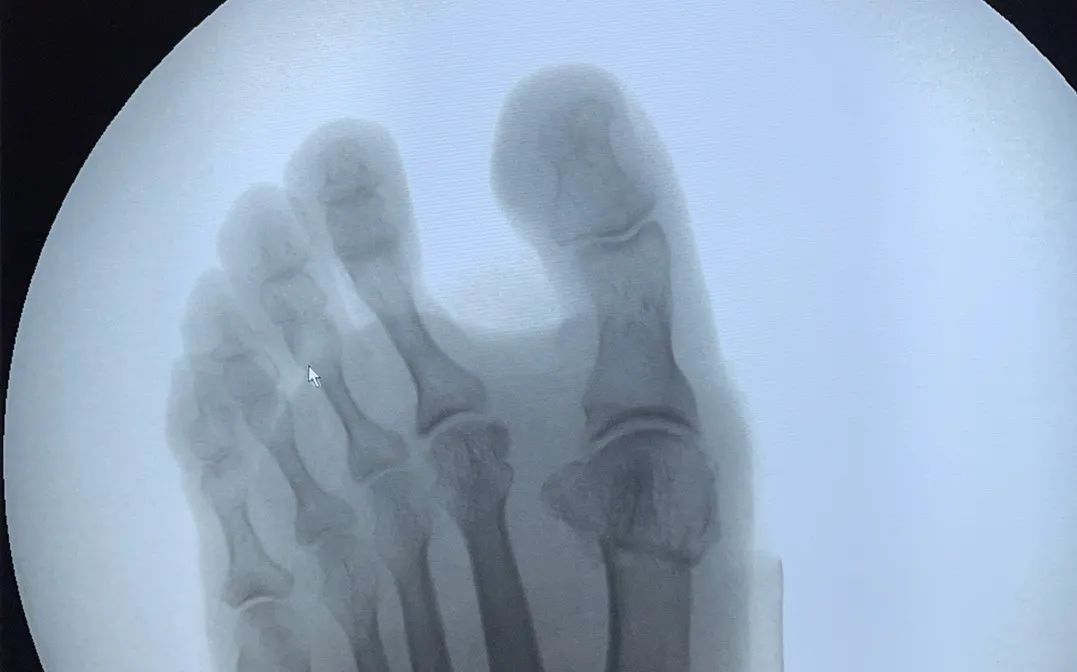

△患者手术前后比对

微创矫形干预拇指外翻的优势

☑ 术后创口仅0.5-1cm

☑ 手术时间双脚仅需30-40分钟

☑ 术后即可穿戴矫正器

☑ 6小时候后可下地行走

☑ 6周后可正常穿鞋生活